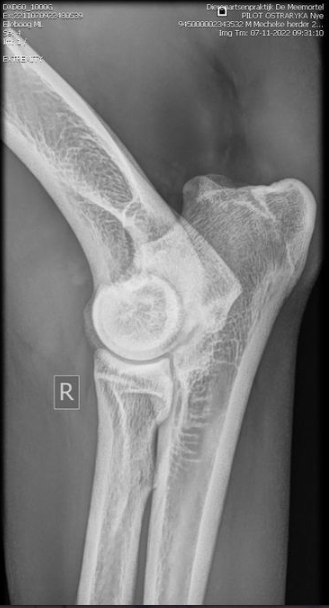

Hips 4/3

Elbows 0/0